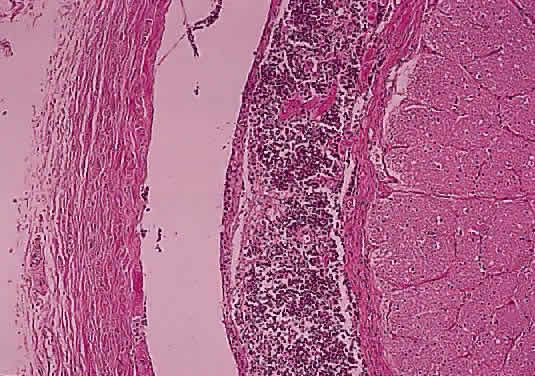

Histologically confirmed metastatic tumors of the optic nerve are uncommon and usually are associated with widespread metastatic disease (Figs. 48 and 49). In only about 1% of cases is the optic nerve predominantly involved.60 The two most common primary sources are breast and lung. Isolated metastasis to the optic nerve is rare; fewer than 20 cases are reported.61–63 Visual disturbance often accompanies meningeal carcinomatosis, typically presenting as rapid visual loss occurring late in the course of the disease. Leukemia and lymphoma may also involve the optic nerve. The frequency with which this is occurring may be increasing because patients survive longer as a result of more effective therapy. Optic nerve involvement by medulloblastoma has also been described.64

Fig. 48. Thickened meninges due to metastases from primary melanoma of the skin (cross-section hematoxylin and eosin staining).

Fig. 49. Amelanotic melanoma cells from primary melanoma of the skin have caused thickening of the meninges (higher power of Fig. 48; hematoxylin and eosin staining).